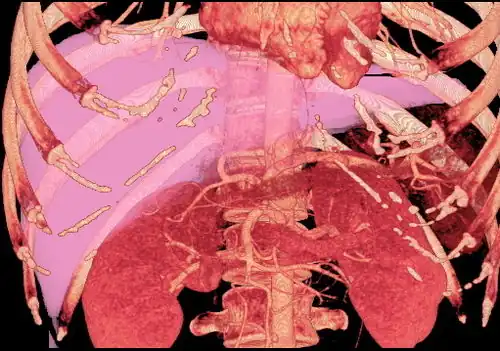

The vast majority of liver transplants use the entire liver from a non-living donor for the transplant, particularly for adult recipients. A major advance in pediatric liver transplantation was the development of reduced-size liver transplantation, in which a portion of an adult liver is used for an infant or small child. Further developments in this area included split liver transplantation, in which one liver is used for transplants for two recipients, and living donor liver transplantation, in which a portion of a healthy person's liver is removed and used as the allograft. Living donor liver transplantation for pediatric recipients involves removal of approximately 20% of the liver (Couinaud segments 2 and 3).